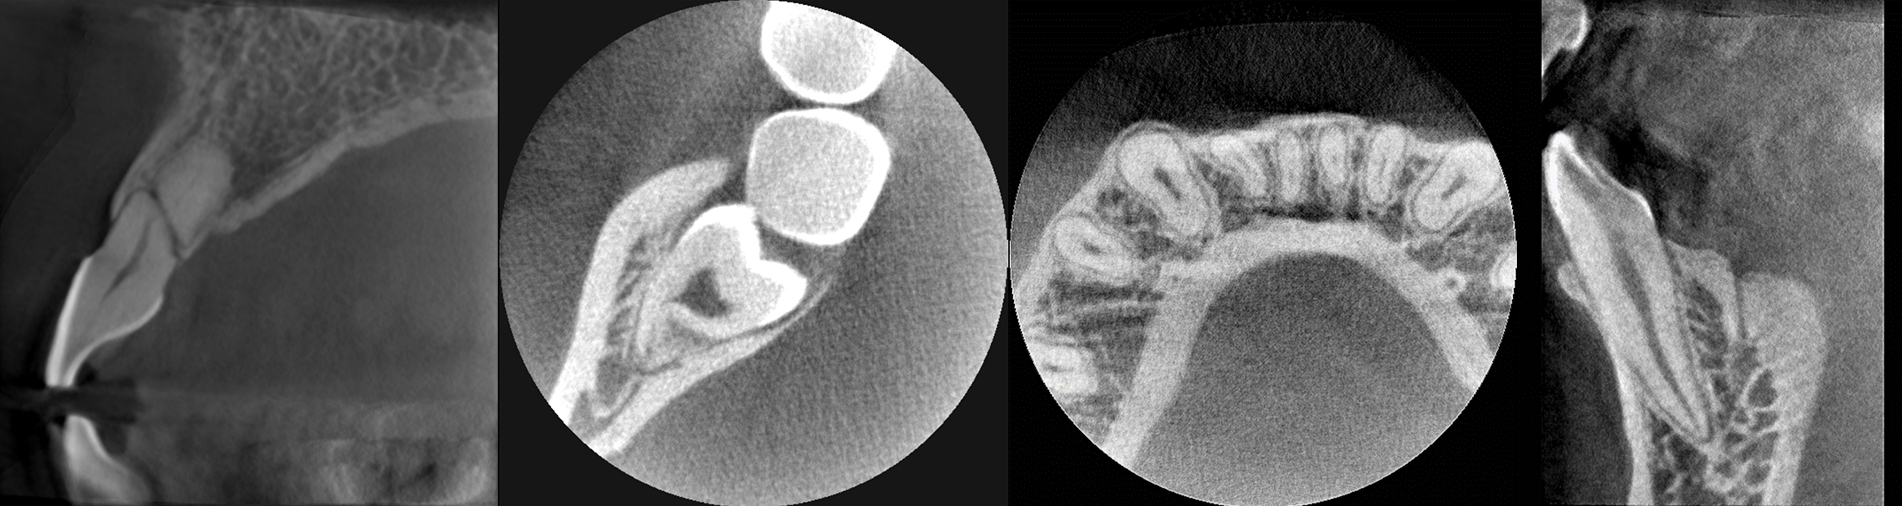

More detail, more confidence

70μm resolution @ 4x3cm

Image reconstruction in 6 seconds

Superior image processing technology